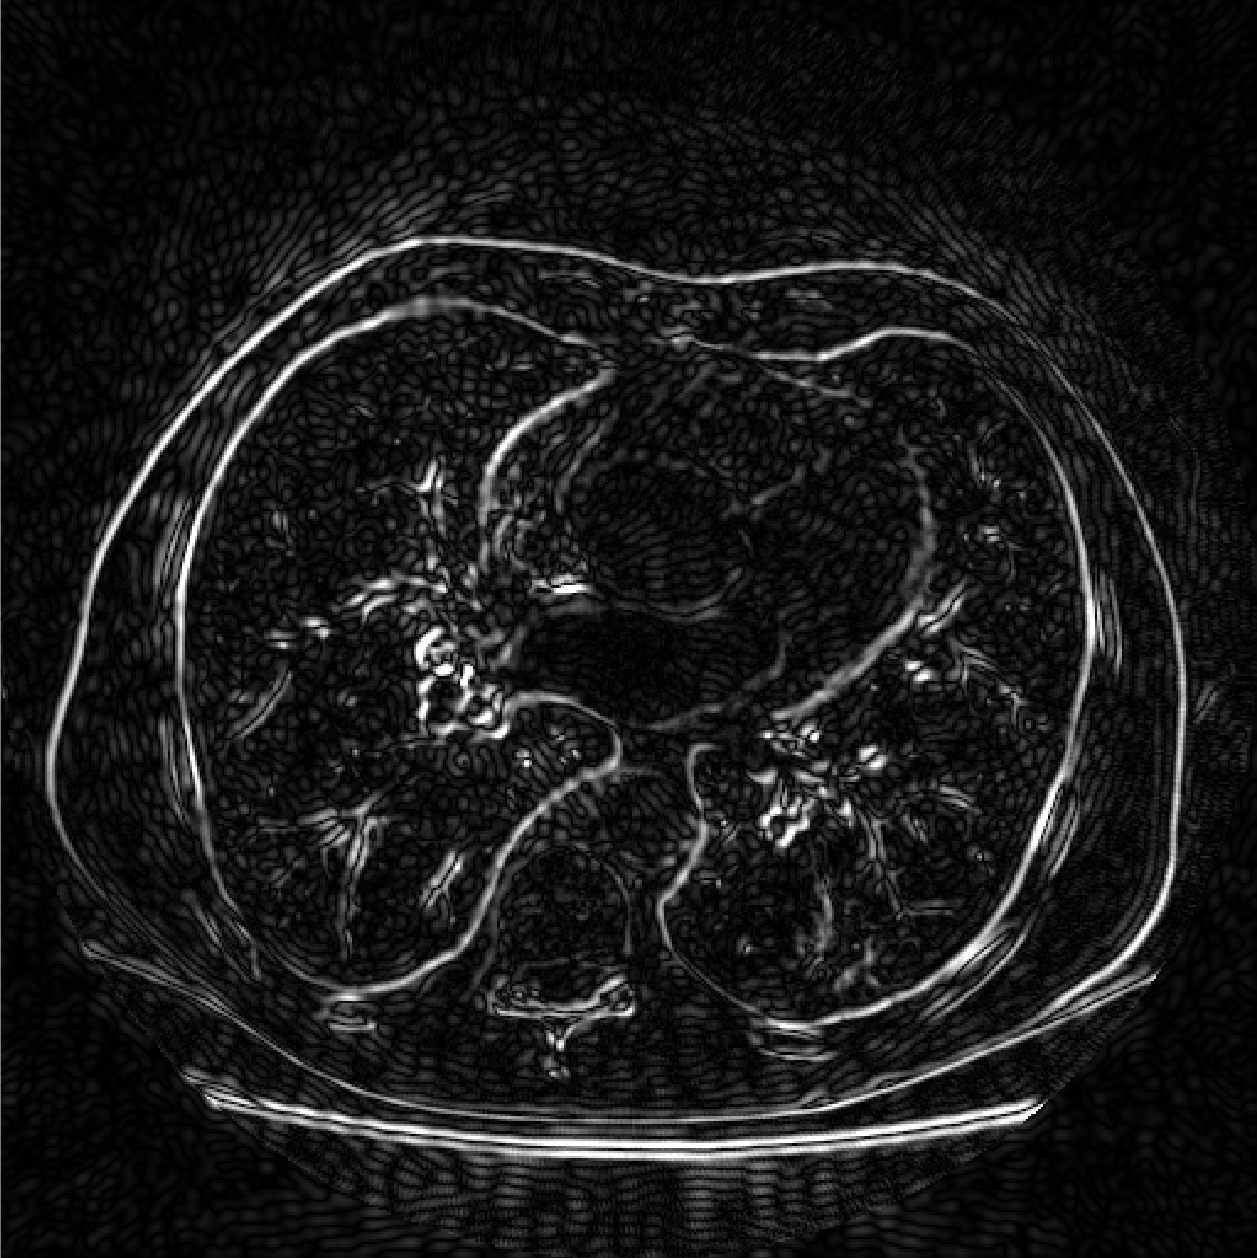

We compare the computation time and SNR of back projection among oblique method, orthogonal method under band limited assumption and box spline methods. We throughly test the performance of oblique method, box spline methods and blurred box spline method (box spline method with detector blur effect). Three images are used in our experiments, the first one consists of randomly placed ellipses, the second one is Forbild head phantom, and the last one is a real CT image from LIDC-IDRI dataset [13] (Fig.2). In our experiments, we fix the sampling steps to be equal in all dimensions, and , where is the downsampling rate. The number of views is set to . Signal to noise ratio (SNR) in dB and structural similarity index (SSIM) are measured for all the methods. All computations were done on one PC (Windows 10 with a 3.7GHz 6-Core Intel Core i7-8700K processors and 32GB of RAM) using Matlab.

(a)

(b)

(c)

Fig.4 shows that our methods provide an improvement over the oblique method in our test cases. Fig.5 shows that our methods are more consistent when the resolution is relatively low. The reason is that oblique method truncates and estimates the sinc function, while we calculate the box spline exactly and have more accurate back projection. Fig.6 shows the absolute total error of the real CT image, the image reconstructed by oblique method suffers from higher error.